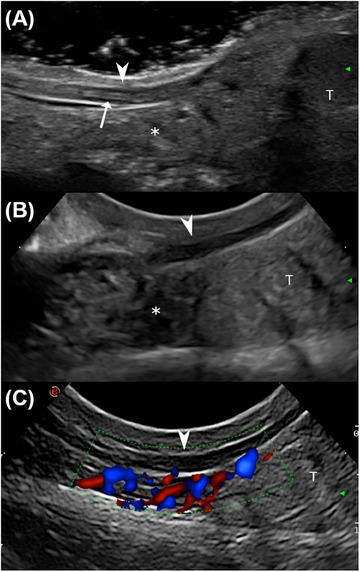

In veterinary medicine, deferent ducts are described as being visible on ultrasound only when pathologically enlarged. Abnormal ultrasonographic enlargement of the deferent ducts has primarily been described secondary to infectious and neoplastic diseases; however, no studies have evaluated the normal ultrasonographic features of these structures. This prospective observational study aimed to describe the ultrasonographic appearance of deferent ducts and assess ultrasound reliability in their identification in intact and neutered dogs without genitourinary disease. The study aimed also to compare ultrasonographic measurements with postmortem anatomical ones and to investigate the relationship between duct identification, size, and intrinsic factors of the patient. The study consisted of ex vivo and in vivo phases in which ultrasonographic assessments of the ducts were conducted at the level of the prostate in longitudinal (location 1) and transverse (location 2) planes and the inguinal canal (location 3) and scrotal region (location 4) in longitudinal planes. A total of 80 deferent ducts were included. The ducts were visible as paired tubular hypoechoic structures delimited by two thin hyperechoic lines, with a target-like appearance on the transverse plane. The deferent ducts were identified in 97.5% of our population in at least one location, with locations 1 and 2 being the most reliable ones. Identification of the ducts was independent of reproductive status; however, reproductive status appeared to be the most significant factor influencing deferent duct size, with neutered dogs exhibiting smaller deferent ducts.